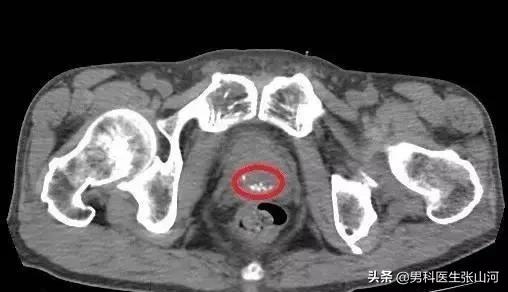

前列腺鈣化灶其實是指在發生前列腺炎時,一些含鈣物質(如磷酸鈣等),與前列腺腺泡或腺管內的細菌、上皮細胞混合而形成的斑塊。隨著這些物質混合,斑塊增大會阻塞腺泡及腺管,隨著斑塊增大,前列腺鈣化灶可形成結石。

大部分前列腺鈣化灶并沒有癥狀,通常是在行B超檢查時發現,所以一般也不需要特別處理。但是當前列腺鈣化灶形成前列腺結石,會出現血尿、尿痛、尿頻、尿急等癥狀,這時就需要手術治療。